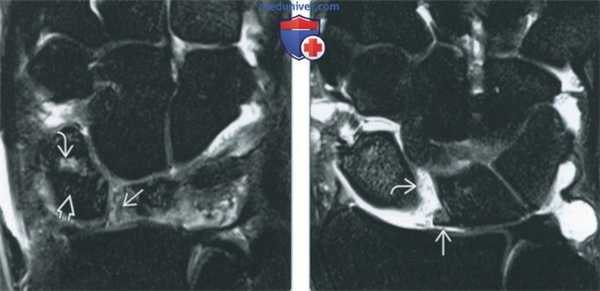

(Слева) МР-артрография в режиме PD FS, сагиттальный срез на уровне полулунной кости: определяются утолщенные луче-трехгранная и тыльная межзапястная в связки, которые имеют аморфную структуру с наличием прослоек жидкости между волокнами. Такая картина характерна для растяжения связок тыла запястья.

(Справа) МР-артрография в режиме PD FS, аксиальный срез через середину запястья, этот же пациент: визуализируются утолщенные связки, которые характеризуются гетерогенной структурой.

• Растяжение тыльных связок запястья:

о Нарушение целостности волокон связки, прослойки жидкости между волокнами

о Как правило, отмечается усиление интенсивности сигнала на Т2 ВИ вследствие отека, воспалительных изменений и кровоизлияний